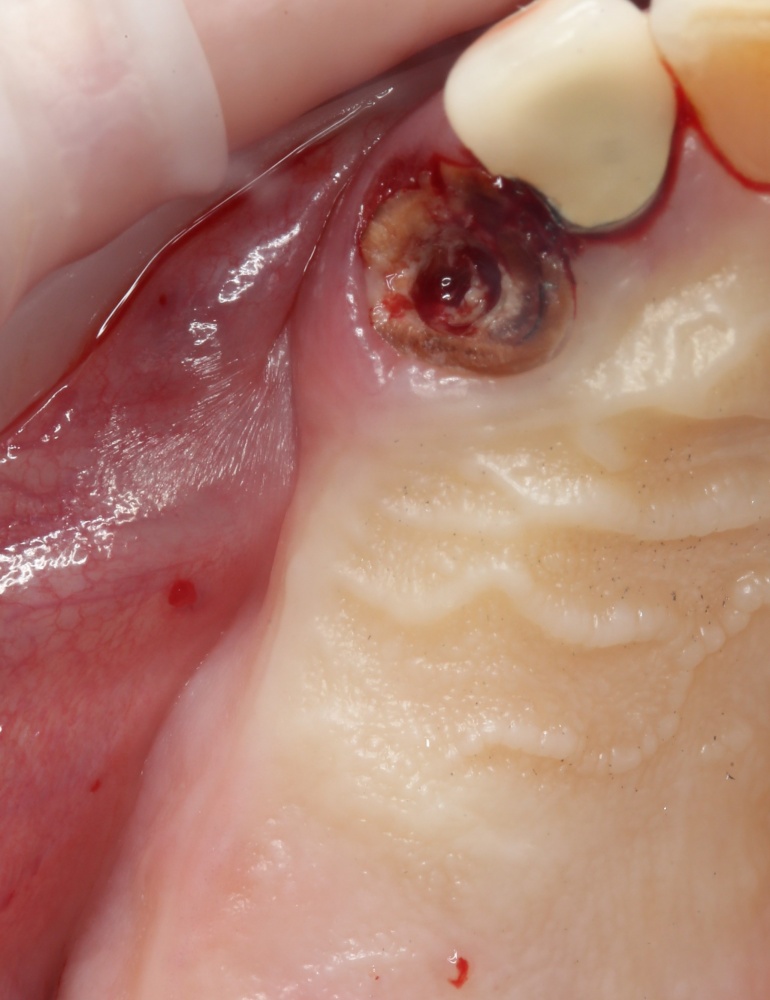

Зуб удаляется по причине периапикального воспалительного процесса, сопровождающегося активной экссудацией и образованием свищевого хода.

После удаления зуба и сопутствующей гранулемы, остается большая по размеру лунка с тонкой и поврежденной воспалительным процессом вестибулярной стенкой: